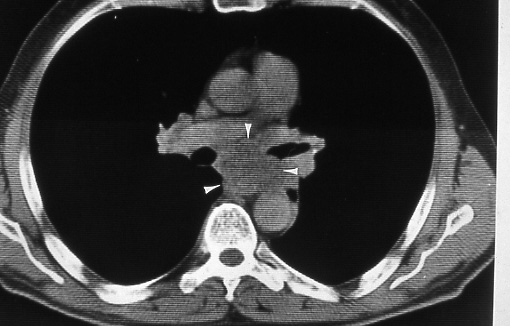

Fig. 26a: Computed tomographic scan of the chest shows enlarged subcarinal nodes (white arrowheads) that deviate the esophagus posteriorly and laterally, N2.